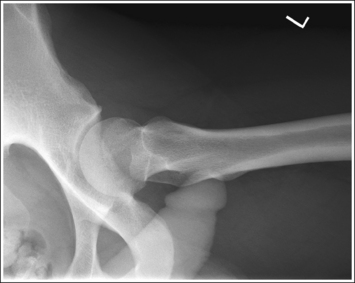

See Figures 7-21 and 7-22 and Box 7-5.

• Regarding the male and female pelves. Be aware of the bony architectural differences that exist between the male and female pelves (Table 7-2). These differences are the result of the need for the female pelvis to accommodate fetal growth during pregnancy and fetal passage during delivery.

Contrast and density are adequate to demonstrate the pericapsular gluteal, iliopsoas, and obturator fat planes of the pelvis.

• Refer to Figure 7-2 for an illustration of each fat plane location.

The pelvis demonstrates an AP projection. The ischial spines are aligned with the pelvic brim, the sacrum and coccyx are aligned with the symphysis pubis, and the ilia and obturator foramina are open and uniform in size and shape.

• An AP projection of the pelvis is accomplished by placing the patient supine on the imaging table, with the legs extended and the arms drawn away from the pelvic area (Figure 7-23). To ensure that the pelvis is not rotated, judge the distance from the ASIS to the imaging table on each side. The distances should be equal.

• Pelvic rotation. A nonrotated AP pelvis projection demonstrates symmetrical ilia and obturator foramina. Rotation is initially detected by evaluating the relationships of the ischial spines with the pelvic brim and of the sacrum and coccyx with the symphysis pubis. The ischial spines should be aligned with the pelvic brim, and the sacrum and coccyx should be in alignment with the symphysis pubis on a nonrotated pelvis. If the pelvis is rotated into a LPO position, the left ilium is wider than the right, the left obturator foramen is narrower than the right, the left ischial spine is demonstrated without pelvic brim superimposition, and the sacrum and coccyx are not aligned with the symphysis pubis but are rotated toward the right hip (see Image 16).

IMAGE 16

• If the patient was rotated into a right posterior oblique (RPO) position, the opposite is true. The right ilium is wider than the left, the right obturator foramen is narrower than the left, the right ischial spine is demonstrated without pelvic brim superimposition, and the sacrum and coccyx are rotated toward the left hip.

The femoral necks are demonstrated without foreshortening and the greater trochanters are in profile laterally, whereas the lesser trochanters are superimposed by the femoral necks.

• Accurate leg positioning. To demonstrate the femoral necks without foreshortening and the greater trochanters in profile on an AP pelvis projection, the patient's leg should be internally rotated until the feet are angled 15 to 20 degrees from vertical and the femoral epicondyles are positioned parallel with the imaging table (Figure 7-24; see Figure 7-21). Sandbags or tape may be needed to help maintain this internal leg rotation. An AP pelvis projection may not demonstrate the proximal femurs with exactly the same degree of internal rotation. How each proximal femur appears will depend on the degree of internal rotation placed on that leg.

• Poor leg positioning. The relationship of the patient's entire leg to the imaging table determines how the femoral necks and trochanters are shown on an AP pelvis projection. In general, when patients are relaxed, their legs and feet are externally (laterally) rotated. On external rotation, the femoral necks decline posteriorly (toward the table) and are foreshortened on an AP pelvis projection. Greater external rotation increases the posterior decline and foreshortening of the femoral necks. If the patient's legs are externally (laterally) rotated enough to position the feet at a 45-degree angle and an imaginary line connecting the femoral epicondyles at a 60- to 65-degree angle with the imaging table, the femoral necks are demonstrated on end and the lesser trochanters are demonstrated in profile (Figure 7-25; see Image 17). If the patient's legs are positioned with the feet placed vertically and an imaginary line connecting the femoral epicondyles at approximately a 15- to 20-degree angle with the imaging table, the lesser trochanter is demonstrated in partial profile and the femoral neck is only partially foreshortened (see Image 18).

IMAGE 17

IMAGE 18

• Positioning for a proximal femoral fracture. Often, when a fracture of a proximal femur is suspected, an AP pelvis projection is ordered instead of an AP hip projection because pelvic fractures are frequently associated with proximal femur fractures. If a patient has a suspected fracture or a fractured proximal femur, the leg should not be internally rotated but should be left as is. Forced internal rotation of a fractured proximal femur may injure the blood supply and nerves that surround the injured area. Because the patient's leg is not internally rotated when a fracture is in question, such an AP pelvis projection demonstrates the affected femoral neck with some degree of foreshortening and the lesser trochanter without femoral shaft superimposition.

The inferior sacrum is at the center of the exposure field. The ilia, symphysis pubis, ischia, acetabula, femoral necks and heads, and greater and lesser trochanters are included within the collimated field.

• Center a perpendicular central ray to the midsagittal plane at a level halfway between the symphysis pubis and the midpoint of an imaginary line connecting the ASIS to place the inferior sacrum in the center of the exposure field. Center the IR to the central ray and open the longitudinal collimation the full 14-inch (35-cm) IR length for most adult patients. Transversely collimate to within 0.5 inch (1.25 cm) of the lateral skin line.

• A 14- × 17-inch (35- × 43-cm) IR placed crosswise should be adequate to include all the required anatomic structures.

• Central ray centering for analysis of hip joint mobility. When an AP pelvis projection is being taken specifically to evaluate hip joint mobility, the central ray should be centered to the midsagittal plane at a level 1 inch (2.5 cm) superior to the symphysis pubis. Such positioning centers the hip joints on the image but may result in clipping of the superior ilia.